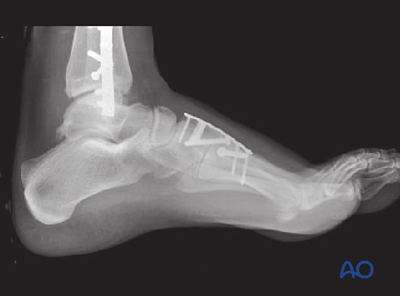

Revised mid- and forefoot modules

This content was revised and extended by Khairul Faizi Mohammad (Malaysia) and Brad Yoo (United States), with Markku T Nousiainen (Canada) and Richard E Buckley (Canada) as executive editors. The content is enriched with the management of Chopart and cuneiform fractures, cuboid and navicular avulsions, as well as with patient assessment and positioning.